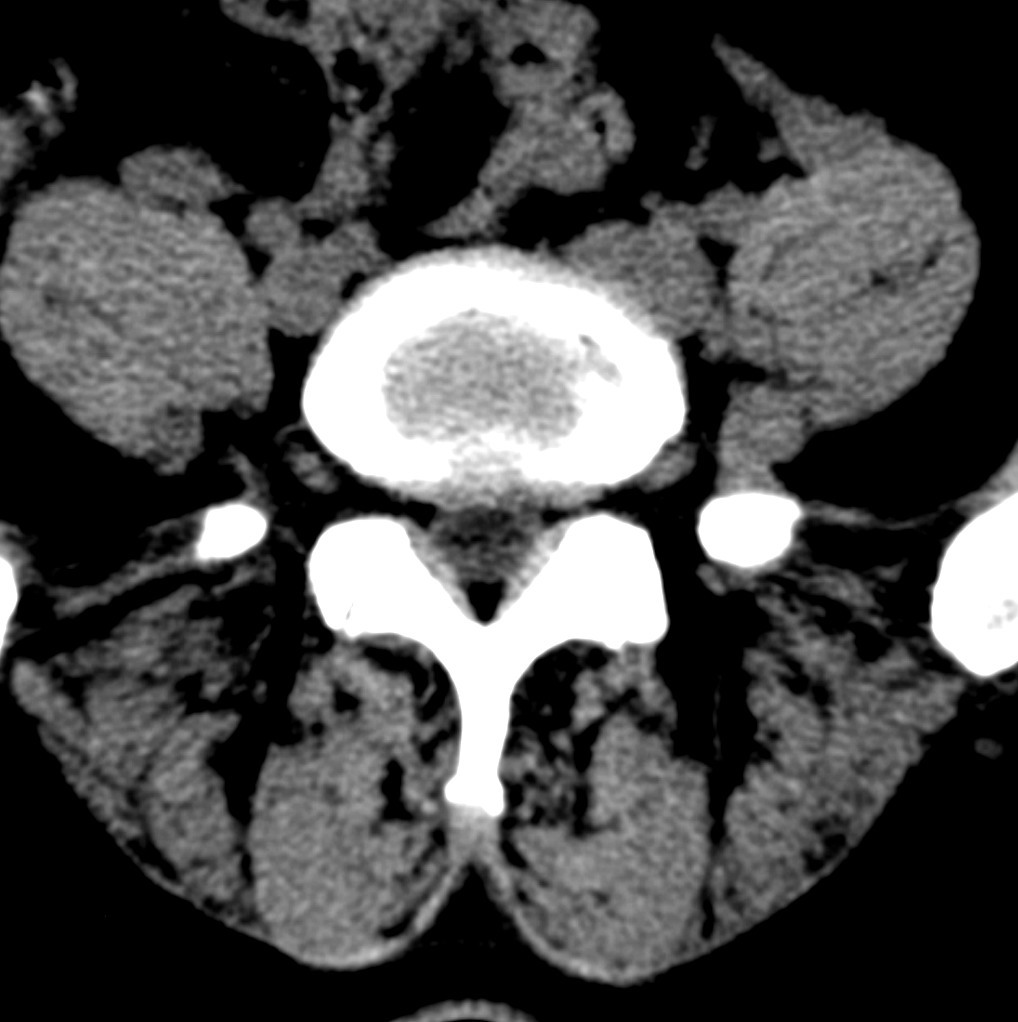

标题: CT19570:是否为腰脱? [打印本页]

标题: CT19570:是否为腰脱?

可以定腰脱否?

大于椎体的环状软组织影,椎间盘膨出

椎间盘膨出伴突出

双边征,考虑滑脱。

椎间盘突出

椎间盘改变并不是很明显,黄韧带似乎有肥厚,